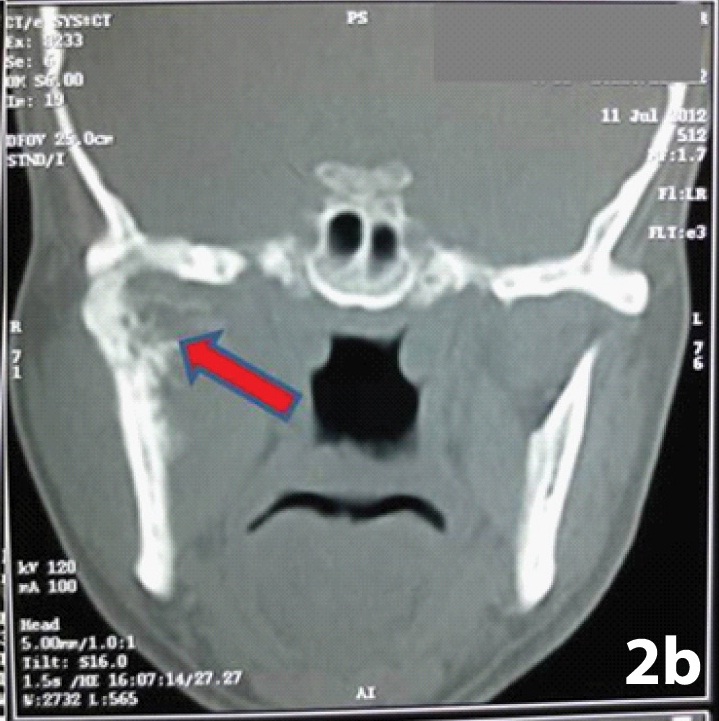

Coronal and axial CT scan revealed an ill defined osseous outgrowth arising from right condyle of mandible showing bony destruction and deformity with soft tissue component and islands of amorphous calcification. The cortex of the lesion was seen destroyed, continuous with that of underlying bone from which it arose and the trabecular pattern was seen merging into the medullary cavity [Table/Fig-2a,b]. The lesion involved the right infratemporal fossa, masticator space and eroded the posterior wall of the maxillary sinus. Such findings of a destructive lytic lesion that too of a short duration favored an underlying malignant process like osteosarcoma, chondrosarcoma or any metastatic tumour of TMJ. Fine needle aspiration cytology of the mass was performed which was non contributory. An incisional biopsy revealed neoplastic chondrocytes in lacunar spaces present in a chondroid matrix, exhibiting pleomorphic and hyper chromatic nucleus. A diagnosis of chondrosarcoma (CS) was made but possibility of chondroblastic osteosarcoma was kept in mind as it was a small biopsy specimen. Investigations like chest radiographs, ultrasound of neck and abdomen and CT of neck were done to rule out metastasis. Segmental resection of ramus was done along with excision of tumour mass that measured about 10 x7 cm. The condyle was resorbed and cut surface of tumour was whitish opaque, peripherally slightly mucoid and with central foci of calcifications [Table/Fig-3a,b]. Microscopically the sections showed typical low grade cartilaginous matrix and pleomorphic chondrocytes in large lacuna with hyperchromatic nuclei and open chromatin pattern, arranged in a lobular configuration. This sharply contrasted the adjacent foci made of pleomorphic spindle cells in storiform pattern [Table/Fig-4a,b]. There were foci of enchondral ossification. No presence of tumour osteoid could be discerned in multiple, serial sections. A final diagnosis of dedifferentiated chondrosarcoma of right TMJ was made. The surgical margins of resected specimen were free of tumour infiltration. On advice of the medical oncologist, the patient received radiotherapy one month post- operatively and remained in a one year disease free follow-up.

Coronal CT scan showing extent of osseous destruction and presence of calcifications (arrow)